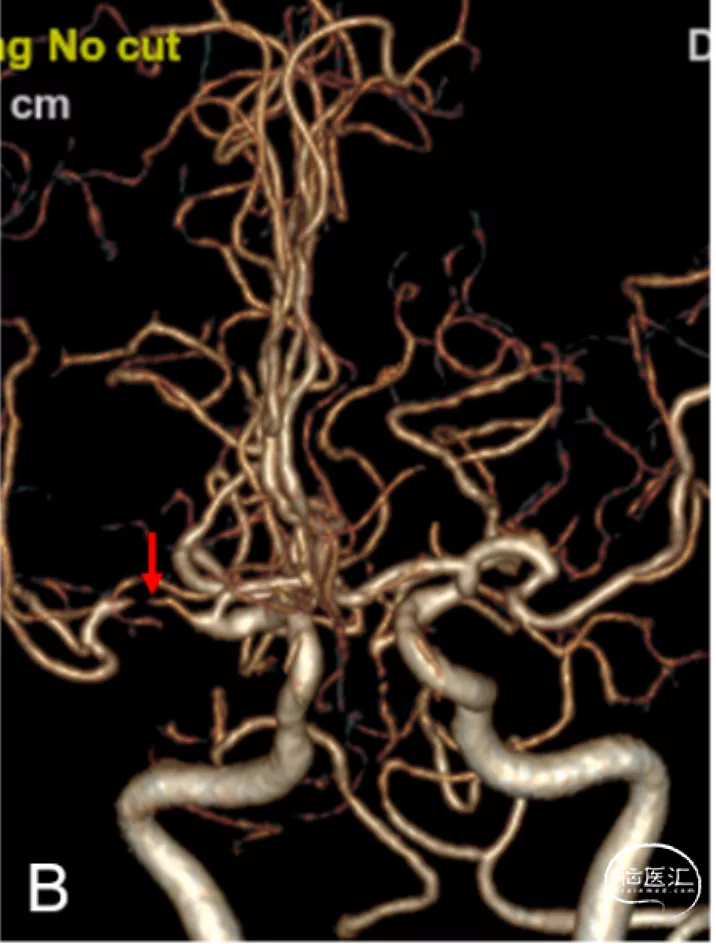

头颈部CTA:右大脑中动脉重度狭窄,左大脑中动脉上干闭塞,双后交通动脉开放向基底动脉返流,双椎动脉发出小脑后下动脉后闭塞(图2A-C)。

图2